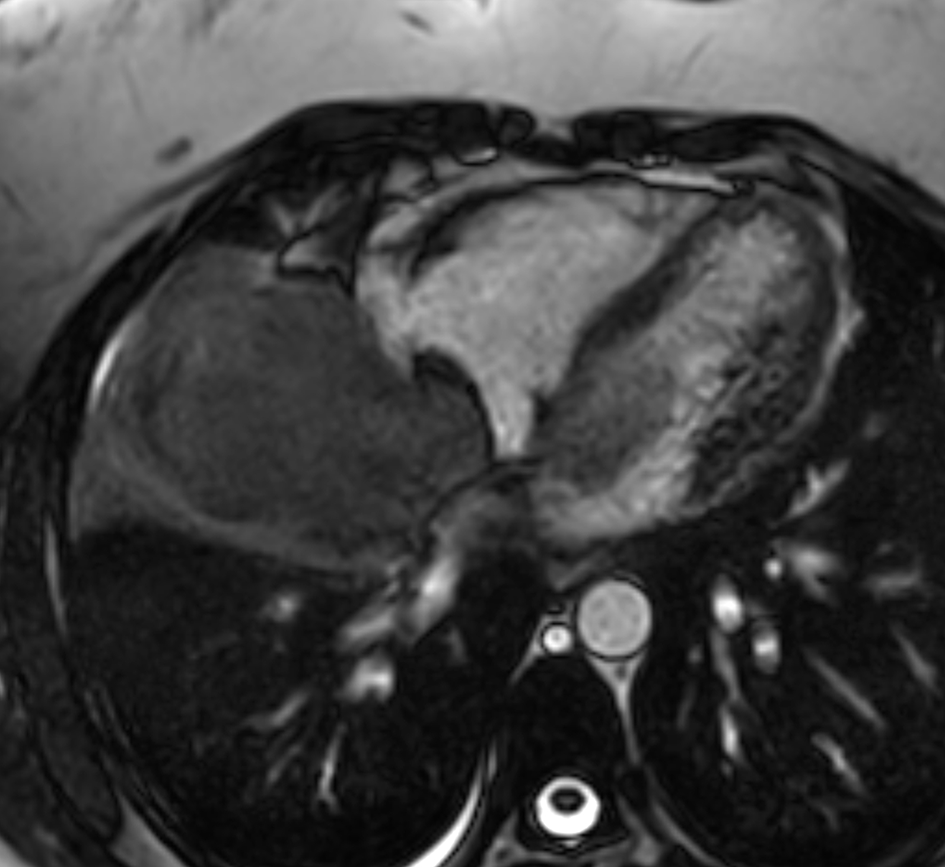

The Cardiac magnetic resonance imaging (MRI) results showed low signal on T1-weighted imaging and high signal on T2-weighted imaging of the mediastino-pulmonary mass (Figure 4). The patient accepted to undergo an urgent mass resection surgery to avoid total mitral valve obstruction and sudden death. The histological study of the resected mass confirmed the metastatic spread of malignant PTs to LA (Figure 5). The patient was discharged from the hospital after having an echocardiographic check-up, which demonstrated no residual tumor. However, three months after the surgery, she died from a huge relapse of mediastinal mass with tracheal invasion.

PTs or cystosarcoma is a rare breast neoplasm.1 These types of tumors are commonly manifested in the breast tissue and are usually benign; however, they might rarely be malignant.2,3 A malignant tumor has a potential to metastasize to distant organs, such as lung, bone, and liver.8 Our case revealed concomitant pulmonary and cardiac metastases, which is unusual, and it is associated with poor prognosis. It has been reported that cardiac invasion could be caused by hematogenous spread, direct extension, or via the lymphatic route.9 In the case of this patient, direct extension from pulmonary metastasis to RIPV is the probable route of metastasis. Reported cases of cardiac metastasis are mostly located in the right heart with the possibility of right ventricle outflow tract obstruction.10 To the best of our knowledge, this is the first case of LA location, complicated by severe mitral obstruction and acute heart failure. The clinical expression of cardiac metastasis is mainly dependent on the tumor burden and location.6 As in the case of our patient, cardiac metastasis can manifest with dyspnea and chest pain, or it can be asymptomatic. Previously, malignant cardiac metastasis had poor prognosis and very rare cases were identified at autopsy.11 However, advances in imaging tools such as echocardiography allows for detection and confirmation of intra-cardiac mass and eventual valve or cavity obstruction. However, echocardiography is limited in the differentiation between PTs, myxoma, fibroadenoma, and thrombus.11 In our case, echocardiography revealed severe mitral obstruction by an intra-LA mass. Cardiac CT and MRI provide multiple views in different axes with a precision of limits as well as intra, and extra cardiac extension, thus allowing a better distinction between the thrombus and other masses.12 The results of the echocardiography, cardiac CT, and MRI for our patient confirmed the intra and extra cardiac location of the tumor and its LA access from RIPV to the mitral valve. Therapeutic approaches, including chemotherapy, radiotherapy, and hormonal therapy are still controversial.7 The surgical excision of cardiac metastasis from a malignant PTs was described in few reports.13 This type of intervention could be an urgent life-saving therapeutic strategy in case of right ventricle outflow obstruction or mitral obstruction, and it can also improve the patient’s quality of life in the short term, as it was in our case.14,15 However, intra-operative mass manipulation could cause tumor dissemination, thus leading to a risk of further metastasis development.11,16 This may explain the hudge relapse of mediastinal mass with tracheal invasion in our patient. In this case report the major limitations were the delay in diagnosing cardiac and pulmonary metastases and the lack of immunohistochemical analysis of the tumor.